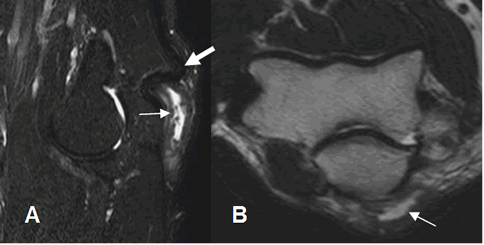

Fig 43 C. Bursitis del tríceps.

A: RM STIR sagital y B: RM axial en T2. Imagen líquida, en la región posterior del codo, (Flecha delgada) en relación con el tendón del tríceps normal. (Flecha gruesa).